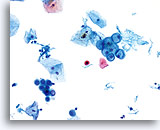

Postpartum Changes

During the postpartum period, or if breast feeding, a hormonal pattern of low squamous maturation predominates. Parabasal cells are abundant, usually presenting singly. Glycogen may also be present. A background of inflammatory cells and reactive changes is often present and may require additional scrutiny. Adherence to strict cytologic criteria (the lack of an increased N/C ratio, abnormal chromatin and irregular nuclear membranes) should preclude an over-diagnosis of cytologic atypia.

Postpartum

High power view of parabasal cells during postpartum. Note presence of glycogen and low N/C ratio. 60X